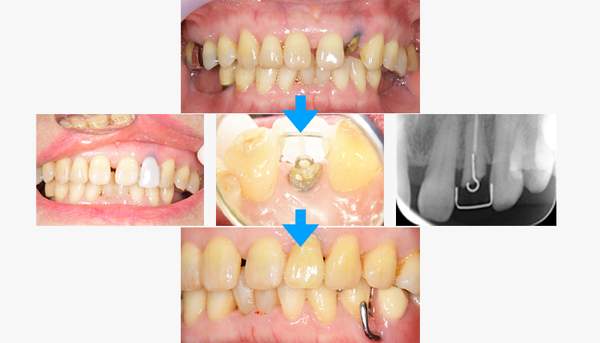

歯が折れててもセラミックは

入れられる?

ケースバイケースですが、歯が割れていなかったり、根の部分がしっかりしている場合は、残せる可能性が高いです。実際写真のように歯に入れていた被せ物がとれていらっしゃった方の症例になりますが、見えている部分はほとんどなく、抜歯の適応でした。

しかし、レントゲンをとると、根の部分は感染がないこと、長さも十分あることから、歯を引っ張り出して残すことにしました。引っ張り出して、再び被せ物を入れられる様にすれば、歯を抜く必要がないですね。

| 年齢 | 70代・女性 |

|---|---|

| 主訴 | 前歯が取れた |

| 治療内容 | 前歯部MTMと同時に審美面の回復。 MTM中に義歯の作成も同時に行う。 最終的に義歯と前歯のクラウンを同時にいれる。 義歯は下顎で、しっかり噛めること、違和感の少ないものという希望があったため、なるべく入れ歯を薄く作成するために金属をしようした義歯とした。 また、見た目もあまり義歯が目立たない様に、バネの部分を見えにくいように作成した。 |

| 治療費 | MTM:110,000円(税込) ファイバーコア:16,500円(税込) E-maxクラウン:110,000円(税込) 義歯:660,000円(税込) |

| 治療期間 | 8ヶ月 |

| リスク・副作用 | 歯にもともと入っていた金属の種類によっては、歯自体の変色を治療で変えられないこともある。 義歯は作ってから痛みがでることがありますが、それは調整を行うことで痛くなくすることができます。 |